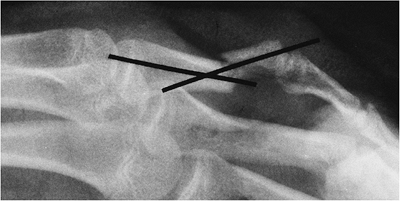

P.595

![]() |

|

FIGURE 9-28 PA (A), oblique (B), and lateral (C) radiographs of a subtle volar plate middle phalanx (arrow) hyperextension injury.